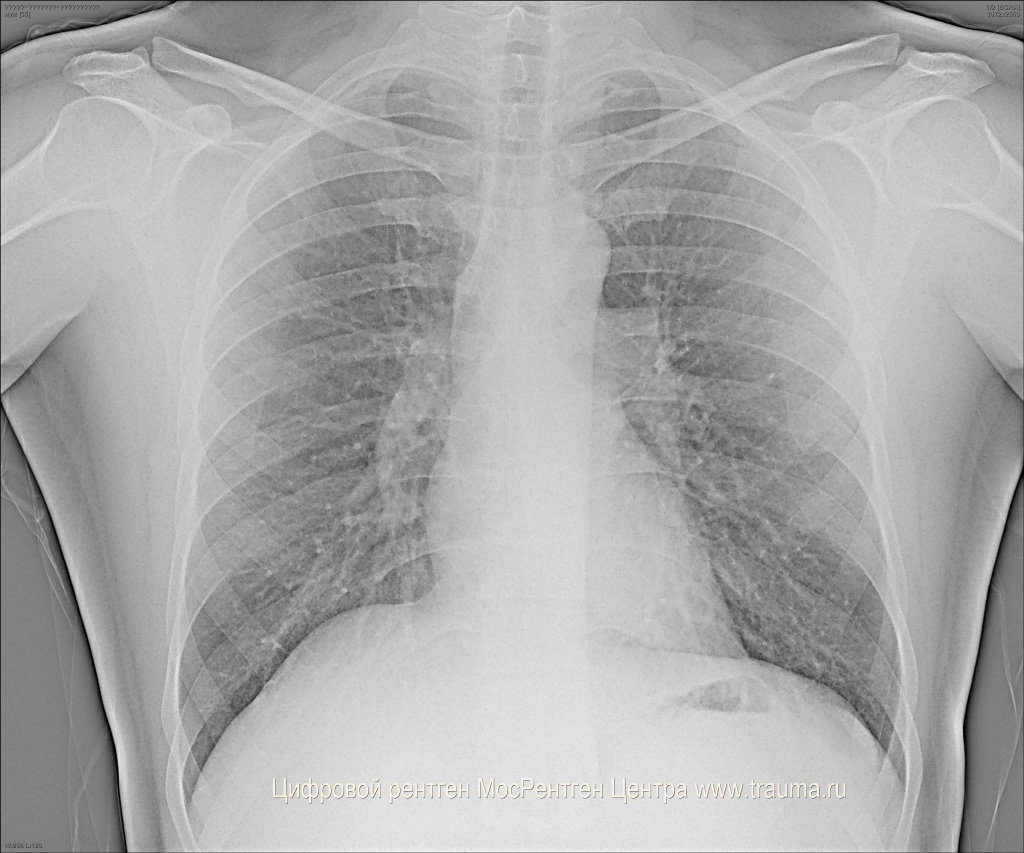

Снимок грудной клетки здорового ребенка: примеры и диагностика

Раздел: Мудрость в объективе